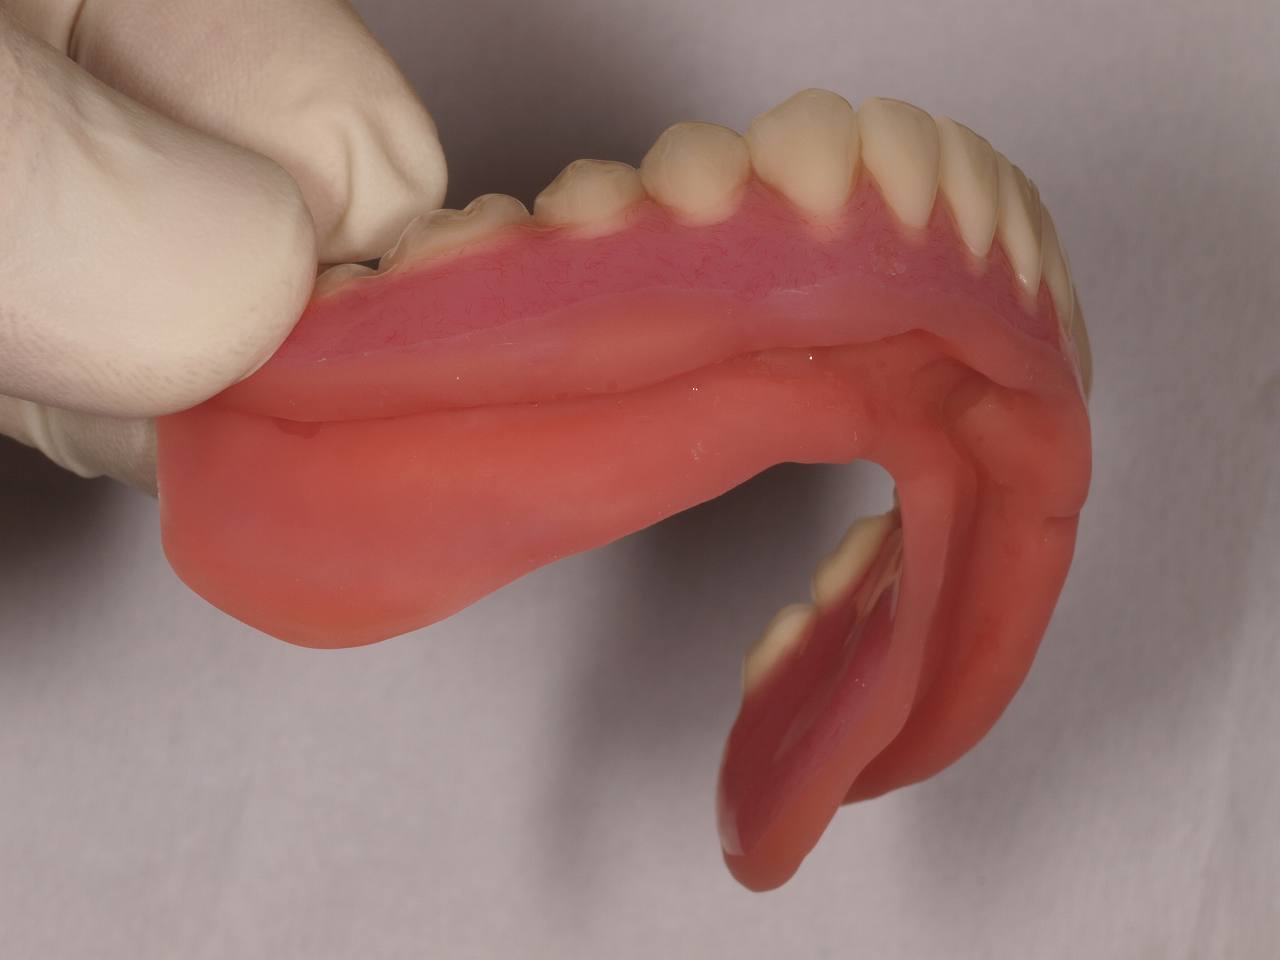

自由診療の入れ歯 上顎は金属床 下顎は柔らかいシリコンを貼り付けた快適な入れ歯|お知らせ |広島市安佐南区の歯科医院 自由診療の入れ歯 上顎は金属床 下顎は柔らかいシリコンを貼り付けた快適な入れ歯 トップ お知らせ・ブログ お知らせ 自由診療の入れ歯 上顎は金属床 下顎は柔らかいシリコンを貼り付けた快適な入れ歯 自由診療の入れ歯 上顎は金属床 下顎は柔らかいシリコンを貼り付けた快適な入れ歯 上顎正面観 2本だけ歯が残っています 右上は弱くなっているためコーヌスにて作成 問題は下顎です 顎堤の高さがなく入れ歯の安定が悪そうです 上顎の金属床 顎堤が吸収した時のためにも公演はレジンにしています 下顎の入れ歯 顎舌骨筋のアンダーカットまでシリコンが維持のために行くようになっています このような外形です Web診療予約 初めての方へ 選ばれ続ける理由 院内設備について 歯が痛いしみる一般歯科 歯がぐらぐらする歯周病 健康な歯を保ちたい予防歯科 子供の虫歯予防をしたい小児歯科 銀歯をセラミックに審美歯科 白い歯を目指しませんか?ホワイトニング 矯正専門医がいるので安心矯正歯科 抜けた歯を補いたいインプラント・入れ歯 医院案内 スタッフ紹介 メリィハウス歯科クリニックオフィシャルホームページ ラベンダー歯科クリニックオフィシャルホームページ お知らせ・ブログ ホーム 診療科目 一般歯科 歯周病治療 予防治療 小児歯科 審美治療 ホワイトニング 矯正歯科 入れ歯・インプラント マウスピース矯正 初めての方へ 院長・スタッフ 設備紹介 医院案内・アクセス メニューを閉じる